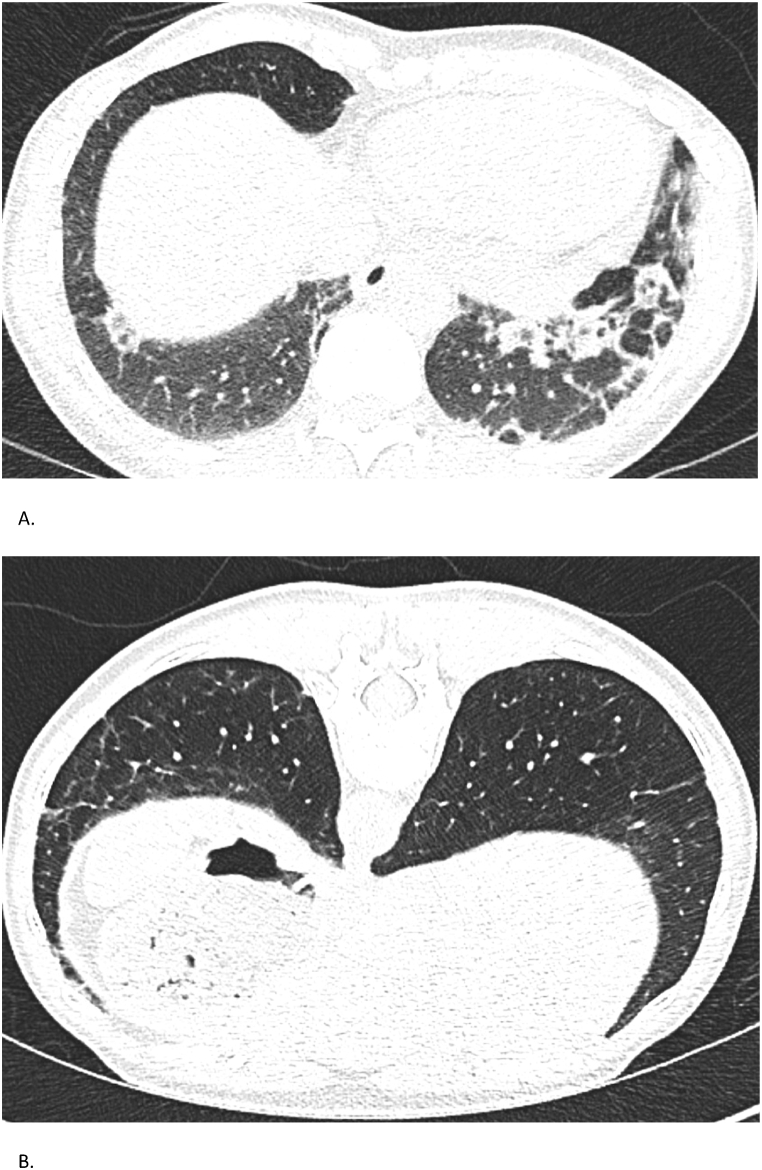

Fig. 4.

Case 4 – Chest CT findings

Serial chest CTs of a 54-year-old woman with anti-MDA5 positive dermatomyositis. (A) CT on September 15, 2023, shows early fibrotic changes and subpleural consolidations. (B) CT on February 14, 2025, demonstrates partial regression of prior abnormalities with new subtle reticulations.

Serologic testing revealed a high anti-MDA5 IgG titer (73 %), decreasing to 30 % by February 2024 and undetectable by January 2025. Myositis- and systemic sclerosis-associated antibodies were negative. Complement levels were normal and cryoglobulins absent. High-resolution CT showed bilateral lower lobe-predominant reticular opacities, subpleural consolidations, and early fibrotic changes (Fig. 4). Lung function showed a restrictive pattern with FVC 3.20 L (84 %) and DLCO of 61 % in June 2023, improving to FVC 3.48 L (93 %) and DLCO 73 % in April 2025.

Fig. 5.

Case 5 – Chest CT Findings

Serial chest CTs of a 53-year-old woman with MDA5-positive ILD. (A) CT on August 3, 2023, reveals widespread ground-glass opacities and consolidations with early fibrosis. (B) CT on April 15, 2025, shows significant resolution with residual subpleural fibrotic changes, estimated at 10–20 %.

Chest CT in August 2023 showed bilateral ground-glass opacities, consolidations, and subpleural reticulation (Fig. 5). Lung function tests revealed a restrictive pattern with FVC 2.07L (73 %) and severely impaired DLCO (45 %). By April 2025, FVC had improved to 2.27L (82 %) and DLCO to 93 %, with CT showing resolution of inflammatory infiltrates and only 10–20 % subpleural fibrosis. Serology showed anti-MDA5 IgG 76 %, an ANA titer of 1:320 (AC-4 pattern), and normal CK and myoglobin. Myositis-specific antibodies, RF, and anti-CCP were negative. Muscle MRI showed inflammation in deltoids, biceps, and gluteal muscles. MMT8 scored 62/80, indicating mild proximal weakness; Frailty Index FI-2 was inconclusive due to language barriers. Skin biopsy revealed interface dermatitis. Cardiac evaluations were unremarkable. Tumor screening and infection work-up were negative.